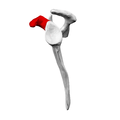

Left scapula. Coracoid process shown in red. Animation. Coracoid process shown in red.

Animation. Coracoid process shown in red. Left scapula. Lateral view. Coracoid process shown in red.

Left scapula. Lateral view. Coracoid process shown in red.